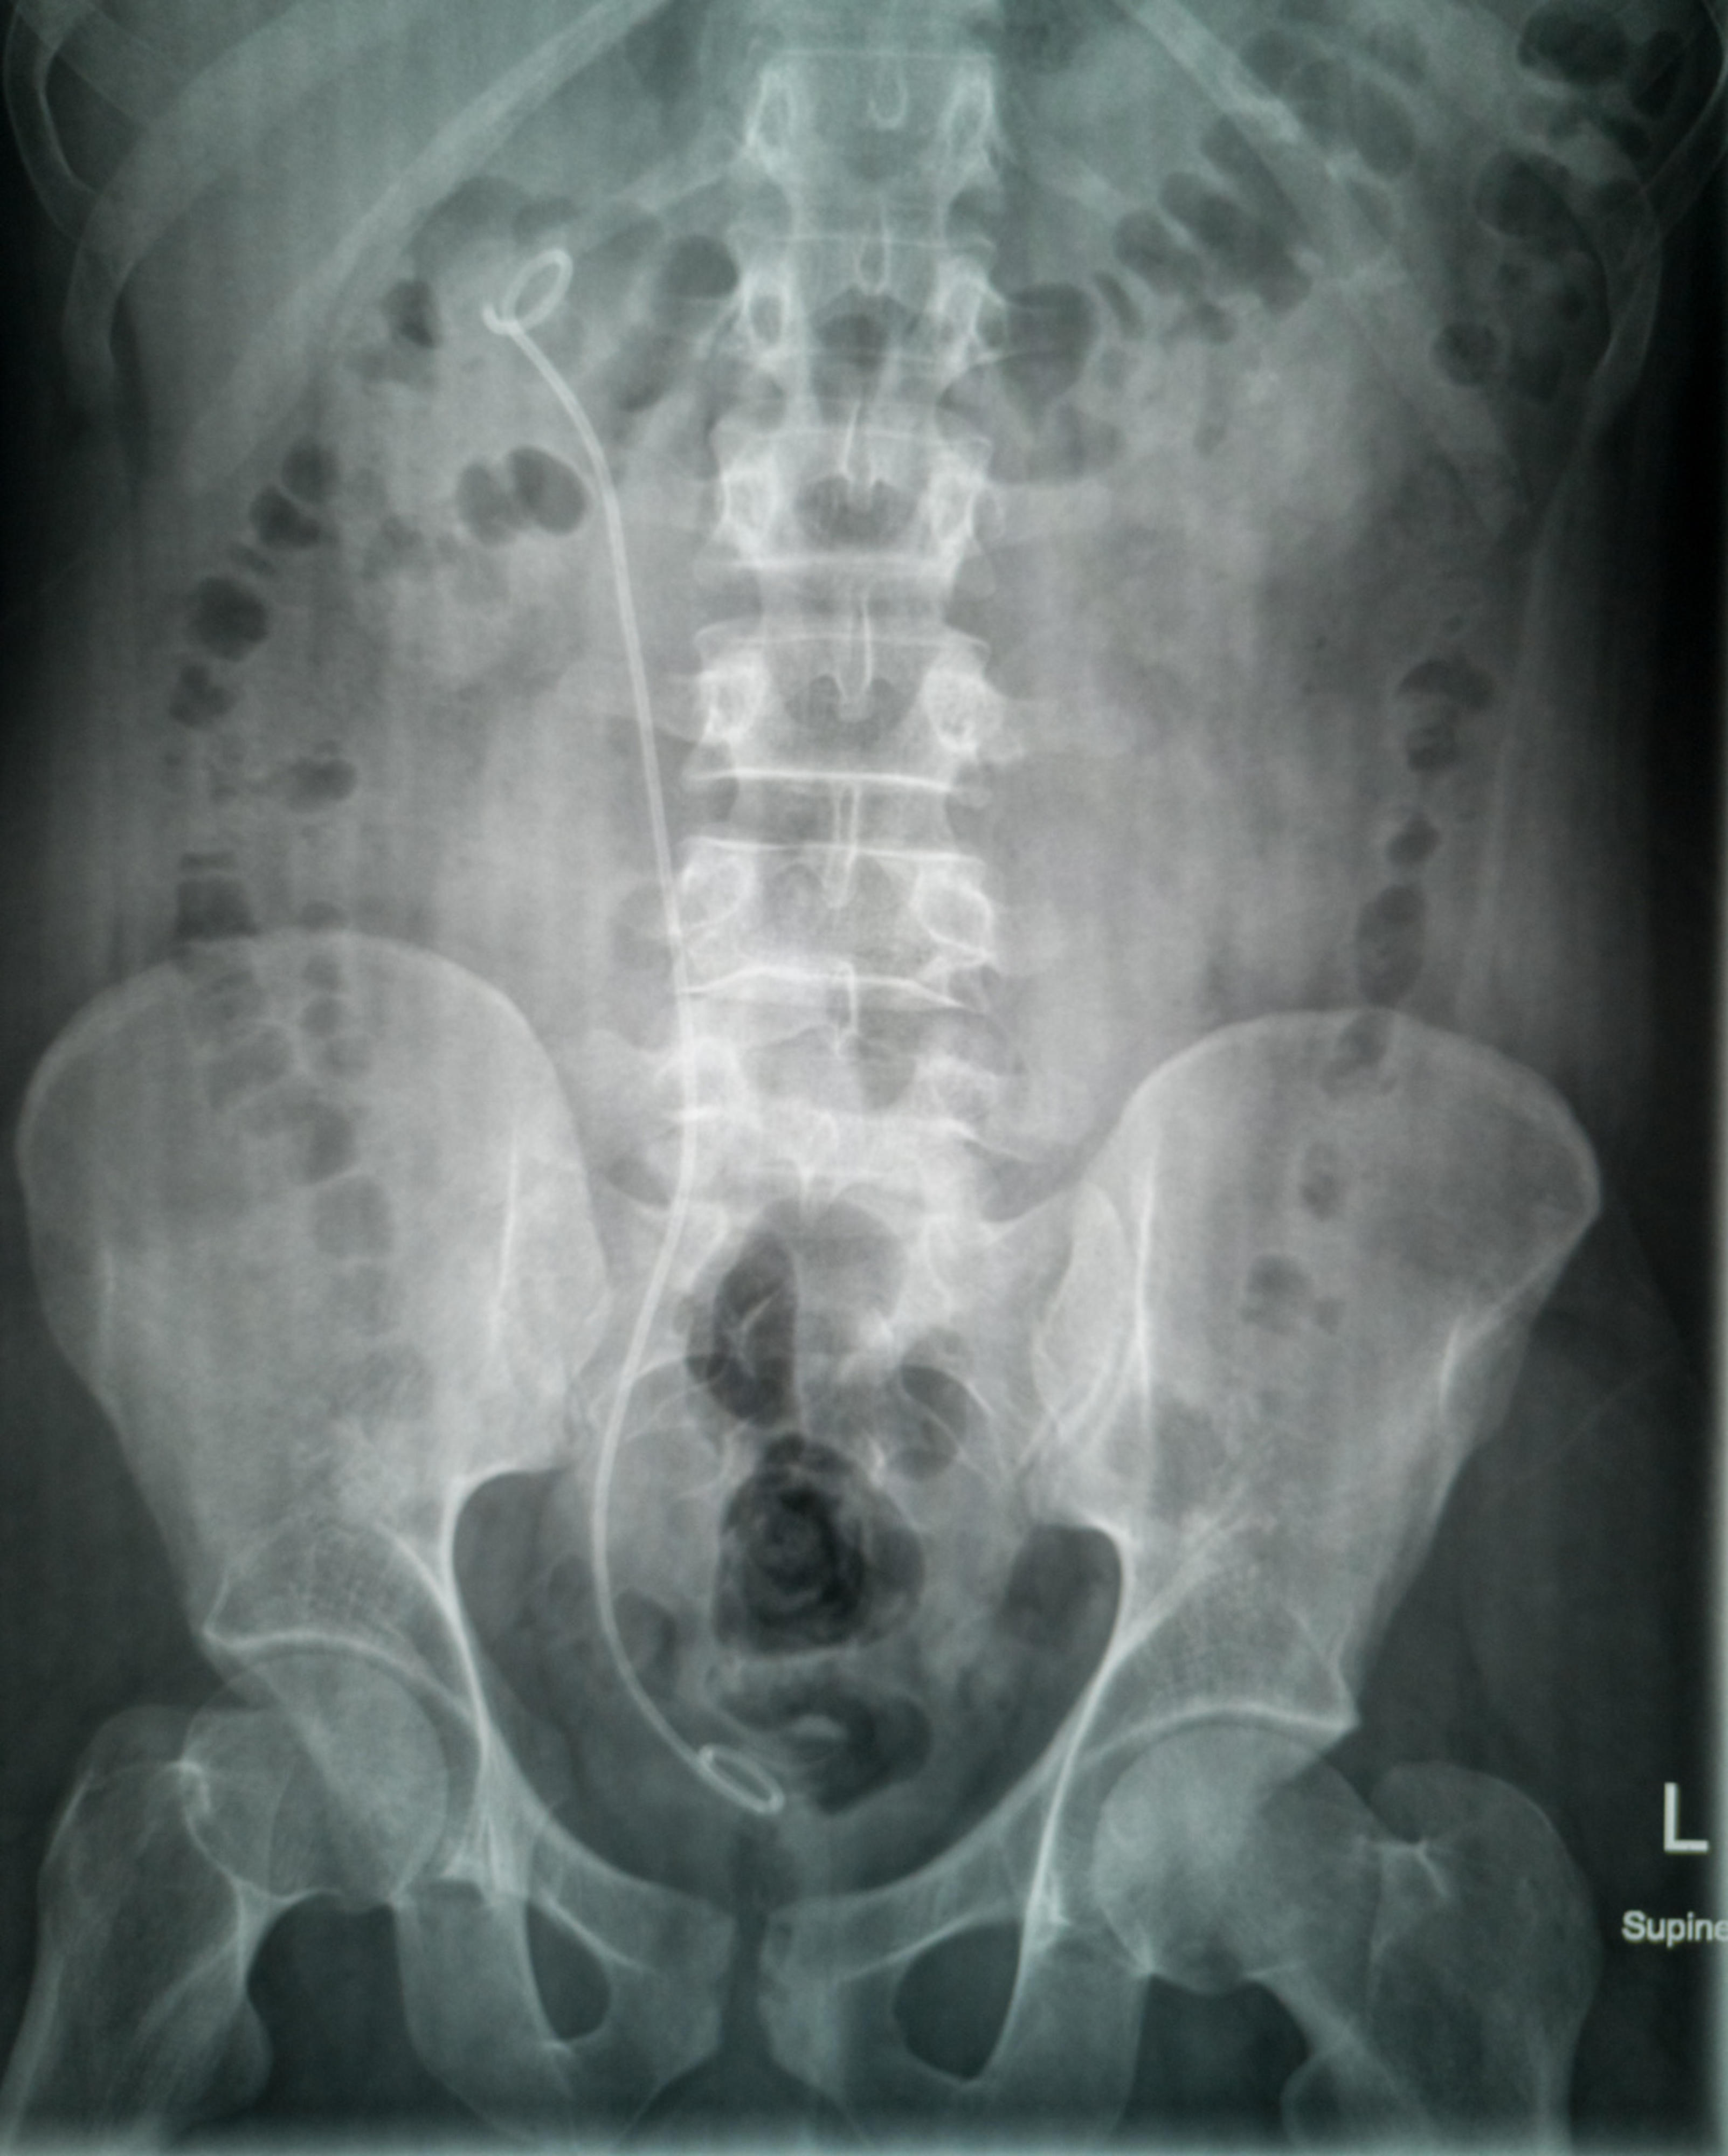

Virtsanjohtimen stentti

Äkillisessä virtsajohtimen kiven aiheuttamassa tilanteessa joudutaan joskus laittamaan ohut muoviletku (stentti) turvaamaan virtsankulkua munuaisaltaasta virtsarakkoon. Stentti asetetaan virtsateiden tähystyksenä. Toimenpide tehdään päivystyksenä, joko leikkaussalissa tai poliklinikalla. Jos kivi ei poistu stentin vierestä itsestään, se poistetaan myöhemmin tähystystoimenpiteellä.

Jos kivimurusia on paljon, asetetaan sisäinen muoviputki eli stentti munuaisaltaasta virtsarakkoon, sillä joskus runsas kivimassa tukkii virtsanjohtimen. Stentti poistetaan myöhemmin poliklinikkakäynnin yhteydessä.